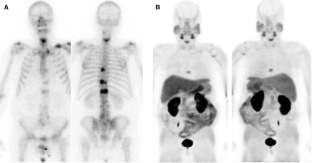

Fig. 1